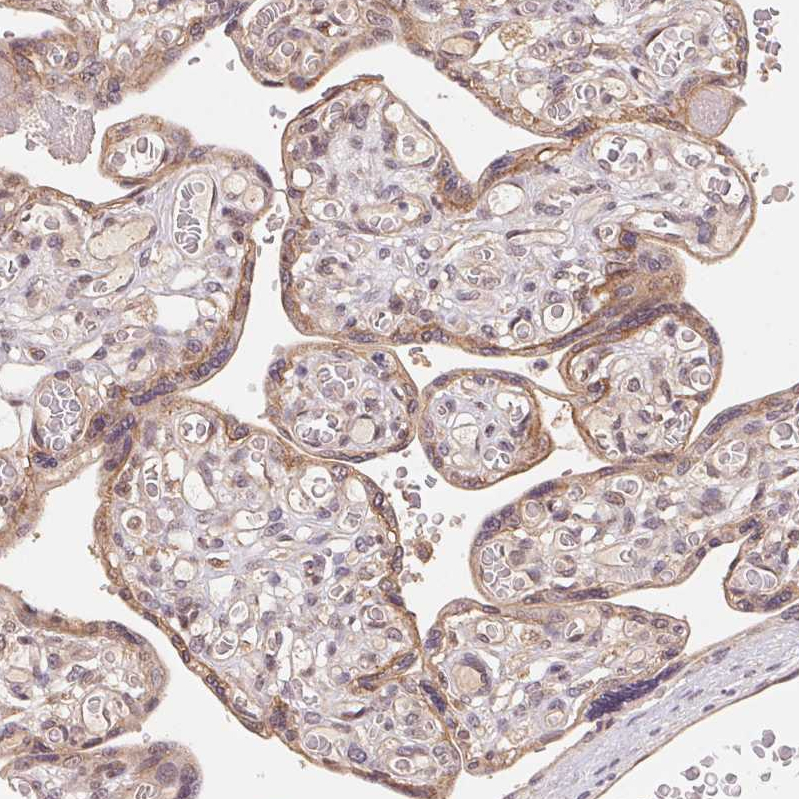

Immunohistochemical staining of human duodenum shows strong membranous positivity in glandular cells.